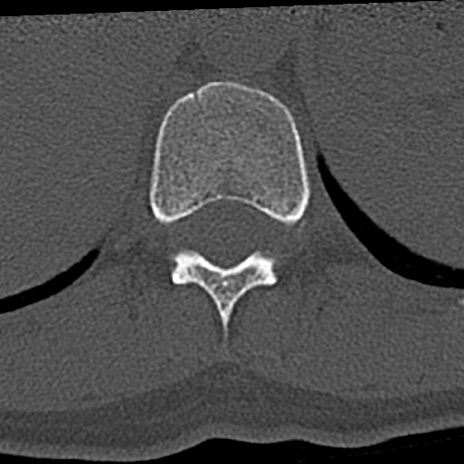

腰椎CT

横断像と矢状断像